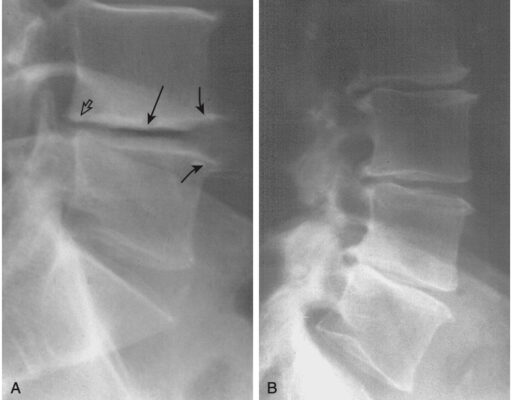

- Hình ảnh thường chụp: phim thẳng, nghiêng. Chụp phim thẳng có thể phát hiện di lệch như vẹo cột sống, trật khớp diện nhỏ. Phim nghiêng có thể đánh giá chiều cao đĩa đệm, trượt đốt sống, thoái hóa đốt sống, thoái hóa khớp, gãy nén ép đốt sống và bệnh khớp diện nhỏ (Hình 2).